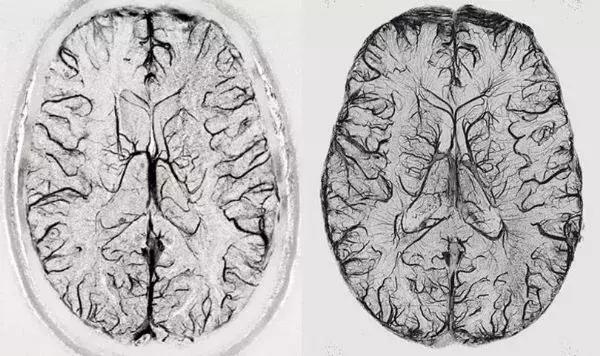

超高场(磁场强度)成像仪的吸引力是显而易见的,然而磁场越强,其信噪比越高,这意味着对物体的成像分辨率更高或成像速度更快。在3T时MRI成像仪能够解析1毫米大小的大脑结构,而在一台7T强度的成像仪下该分辨率就能达到0.5毫米,这就足以识别人类大脑皮层内部的功能单元,或许还能够观察到人类大脑中神经元连接之间的信息流,而具有更高场强度的成像仪预期的分辨率至少是7T设备的两倍以上。

较好的分辨率也是喜忧参半的,因为其会使得成像仪对轻微的运动变得高度敏感,而一些由呼吸或心跳引起的机体重复运动或许也是可以被模拟或移除的。研究者Menon说道,最大的挑战就是7T甚至更高,这种强度目前在较低分辨率的成像仪中并不存在。如今7T强度的成像仪能通过揭示小于1毫米的结构来为研究人员开启研究人类活体大脑的新视野。

在被揭示的结构中有6层大脑皮层,3毫米厚得到大脑外层区域主要负责人类高水平的认知能力,而且每一层都非常特殊,一种负责处理来自大脑其它区域的信息输入,一些则进行信息处理并将处理结果传递到大脑的其它部分中。

7T磁通量的成像仪能够更好地帮助测定大脑的连接性,研究人员旨在完全绘制出大脑神经元间的连接,如今他们利用3T和7T的成像仪对184名个体进行了扫描,相比3T而言,在7T磁通量下,研究者能够检测到神经元之间的沟通以及较多的神经网络,这或许对于未来研究人员准确预测人类疾病至关重要。

利用7T成像仪能够帮助解析更多多发性硬化症的症状和疾病进展机制,而用于治疗该病的药物也能够帮助减缓患者机体运动缺陷的进展,同时还能确保患者的预期寿命和生活质量。

研究者Menon表示,利用7T成像仪我们就能定位此前观察不到的损伤位点,包括背外侧前额叶皮质,该区域主要负责机体的执行功能和注意力,而从历史角度来讲这是很难观察到的,观察到的这些病变也能够帮助解释为何患者会出现一些认知上的症状。